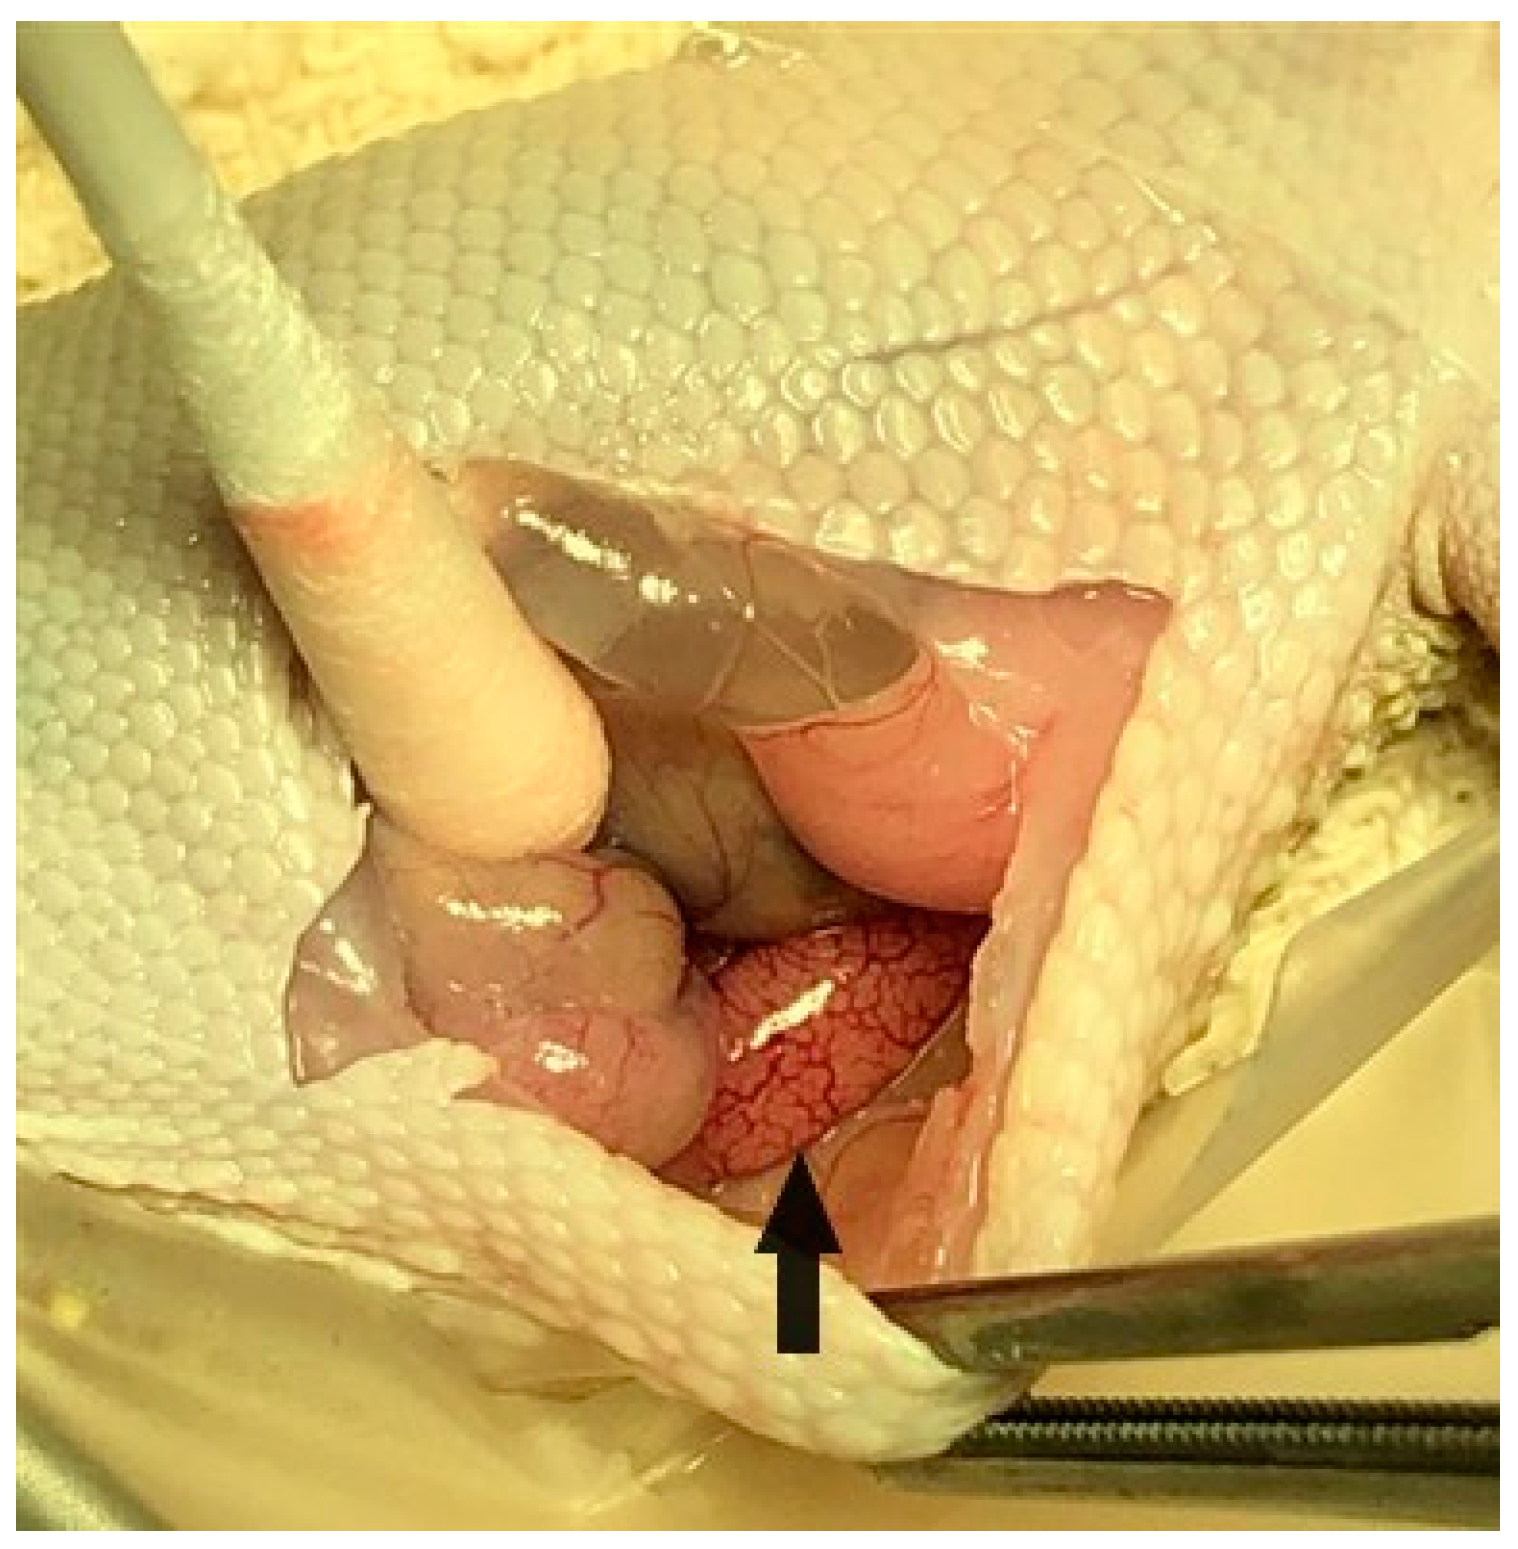

2.8. Unilateral Orchidectomy and Epididymectomy Procedures

On day 63 of the study, all twenty-four geckos underwent a surgical procedure to remove their right testicle and epididymis for morphometric measurements and gross and histopathological assessment. Each gecko was already anesthetized with isoflurane inhalant gas for venipuncture, ultrasound, and electrostimulation, and was administered subcutaneous injections of dexmedetomidine (Zoetis Services LLC, Parsippany, NJ, USA) 0.025 mg/kg, hydromorphone (Hospira, Inc., Lake Forest, IL, USA) 0.5 mg/kg, and meloxicam (OstiLox, VetOne, Boise, ID, USA) 0.3 mg/kg for additional sedation and analgesia just prior to surgery. Anesthesia was monitored throughout the procedure by measuring the respiratory rate, Doppler heart rate, and presence/absence of muscle tone and reflexes. The geckos were placed in dorsal recumbency, and their surgical site (ventral right abdominal region) was aseptically prepared with chlorohexidine scrub (VetOne, Boise, ID, USA) and 0.9% sterile saline. A #11 scalpel blade (Bard-Parker, Aspen Surgical Products, Inc., Caledonia, MI, USA) was used to make an initial paramedian incision on the right side of the abdomen, and Metzenbaum scissors were used to extend the body wall incision (3–4 cm). A Lone Star self-retaining retractor (Cooper Surgical Inc., Trumbull, CT, USA) was used to enhance visualization within the coelomic cavity. The ventral aspect of the intra-abdominal fat pad was immediately visualized upon entering the coelomic cavity. Gentle retraction of the fat pad revealed that the thin-walled urinary bladder was adhered to the dorsal wall of the fat pad. Medial displacement of the intestines using a cotton tipped applicator (Puritan Medical Products, Guilford, ME, USA) revealed the right testicle (Figure 3) and epididymis along the dorsal body wall (Figure 4). Once in the visual field, the thin mesorchium at the cranial pole of the testicle was gently grasped with atraumatic forceps to aid in the exteriorization and visualization of the testicle. A small hemoclip (Titanium ligating clips, Weck, Morrisville, NC, USA) was placed on the testicular artery and veins to control hemostasis, and the testicle was dissected from the remainder of the mesorchium for removal. The remaining epididymis was then grasped at its cranial end and traced caudally so an additional hemoclip could be placed and the epididymis removed. Unfortunately, it was challenging to remove the testicle and epididymis en bloc. Sterile cotton tip applicators were used to apply pressure for additional hemostasis as necessary, and the abdomen was flushed with sterile saline prior to closure. The body wall was closed with 4-0 Maxon (Coviden, Mansfield, MA, USA) in a continuous pattern, and the skin was also closed with 4-0 Maxon using a horizontal mattress pattern. Sterile skin glue (GLUture, Zoetis, Kalamazoo, MI, USA) was applied to the incision to reduce seepage. A subcutaneous injection of atipamezole (Zoetis Services LLC, Parsippany, NJ, USA) 0.5 mg/kg was administered to reverse the dexmedetomidine. The geckos were monitored post-operatively until all reflexes had returned and they were able to ambulate normally. Each animal received an additional injection of hydromorphone 0.5 mg/kg subcutaneously the following day, in addition to 0.3 mg/kg meloxicam subcutaneously once daily for three consecutive days to minimize discomfort. Animals were observed daily for 6 weeks, post-operatively, for any negative side effects associated with the surgical procedure, including anorexia, depression, discharge or swelling at the incision site, dehiscence, and lack of energy or ambulation.